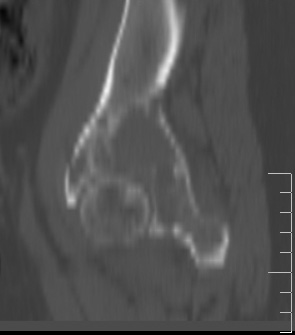

Сохранная по соматической патологии женщина ,47 лет. В 1996 г. установлен диагноз- cr левой молочной железы Т2N1Mo (2б)- проведено комплексное лечение- мастэктомия по Холстеду, ДГТ, 5 курсов ПХТ по схеме CMF. Сейчас менопауза уже 6-7 лет. В декабре 2004 года на профилактической остеосцинтиграфии с Тс99- выявлен единичный очаг повышенной фиксации препарата в зоне правой седалищной кости, рекомендована Рентгенография костей таза, выполнена- без патологии. УЗИ брюшной полости и Р-графия легких от конца апреля 2005 года - без патологии. Приблизительно 3 месяца назад появился болевой синдром в правом т/бедренном суставе с тенденцией к усилению. На рентгенограмме таза от мая 2005 года по заключению Рентгенолога очагов остеодеструкции не выявлено. Сегодня сделал ей Кт костей таза (картинки в приложении)- очаг деструкции в правой седалищной кости в зоне крыши вертлужной впадины.Что можно и нужно сделать? Жду советов, мнений, предложений по дальнейшей тактике ведения больной. С уважением, Корнев А.В.